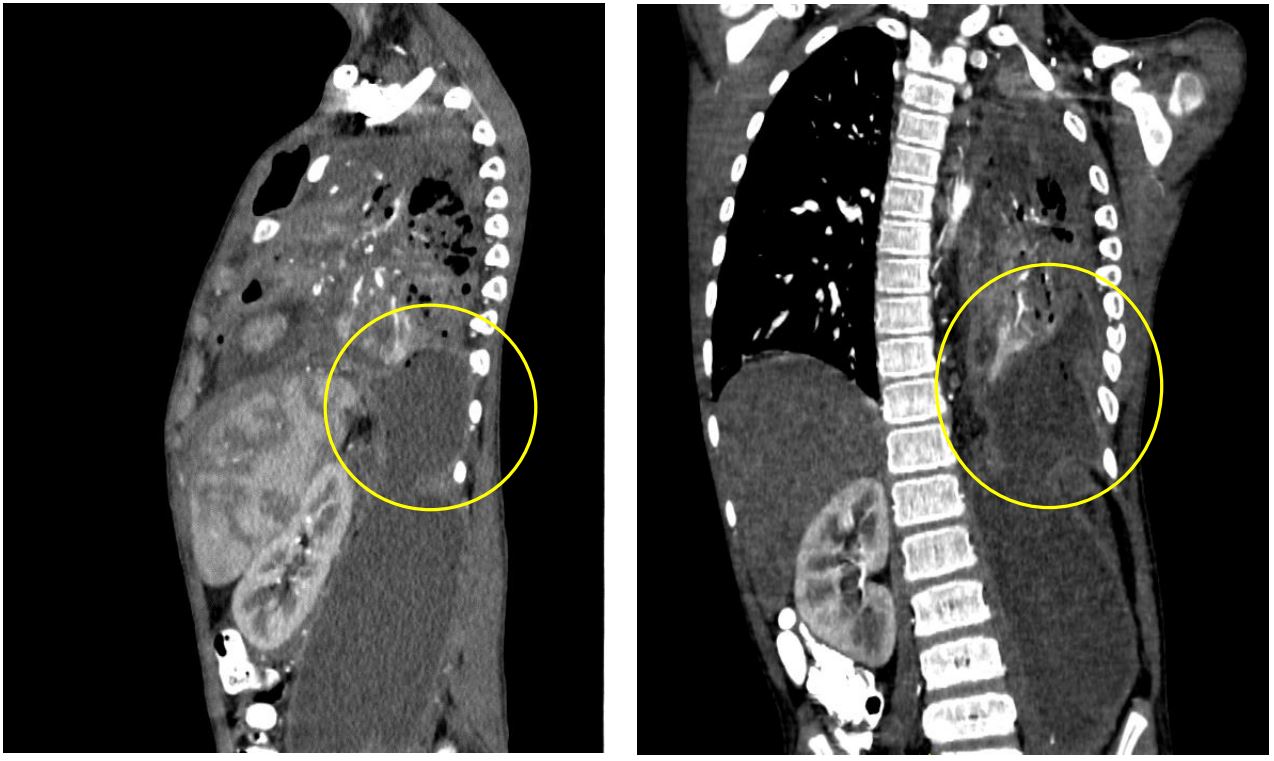

Figure 6: Contrast-enhanced CT scan (axial view) showing rim-enhancing hypodense collection with air-fluid layering in the left anterior chest wall (yellow circle), suggestive of empyema necessitans

Any infectious process that spreads to the psoas muscle can progress into the posterior mediastinum and cause pleural complications [5-9]. Several routes and mechanisms have been described such as direct erosion through the diaphragm, trans-diaphragmatic migration of infected abdominal fluid, or as insinuated this case, a probable congenital diaphragmatic defect which is the proposed route for ascending retroperitoneal infection into the thoracic cavity causing empyema thoracis and subsequently empyema necessitans (Figures 5,6) [5-7]. Empyema thoracis is defined by the presence of frank pus in the pleural space and commonly from extension of a pulmonary infection. Moreover, Pleural complications secondary to an ascending abdominal infection is relatively rare [6].